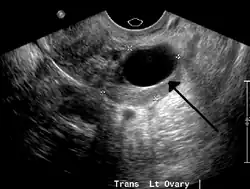

Transvaginal ultrasonography of a hemorrhagic ovarian cyst, probably originating from a corpus luteum cyst. The coagulating blood gives the content a cobweb-like appearance. -

Ovarian cysts are usually diagnosed by pelvic ultrasound, CT scan, or MRI, and correlated with clinical presentation and endocrinologic tests as appropriate.[15] Ultrasound is the most important imaging modality, as abnormalities seen in a CT scan sometimes prove to be normal in ultrasound.[5][8] If a different modality is needed, then MRIs are more reliable than CT scans.[5]

Ultrasound

Usually, an experienced sonographer can readily identify benign ovarian cysts, often with a level of accuracy that rivals other approaches.[5]